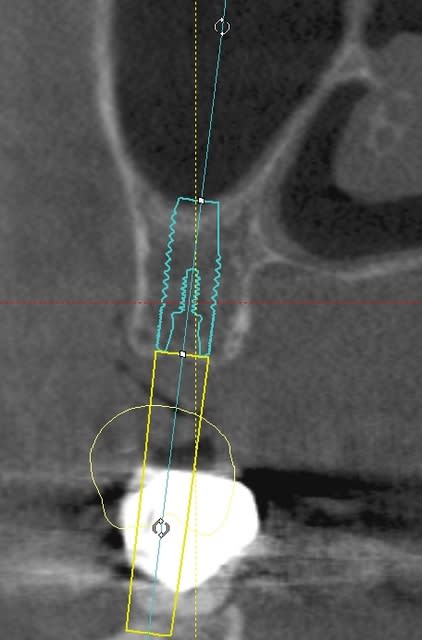

une petite étude de ton cas avec implants osseosped Astra :

12 : 3.5 x 11

13 : 3 x 11 (?)

14 : 3 x 11 (?)

15 : 3.5 x 11 (?)

16 : 4 x 11

17 : 4 x 11

je ne pratique pas donc pas de conseils sur ces implants.

techniquement:

extraction de 12 , curetage soigneux.

vue la qualité osseuse :

si D4 :

saignée à la lame n°15

si D3 :

avec un disque diamanté 10 x 0.3mm incision crestale de 12 à 16 ou 17

puis avec un disque de 20x0.3mm ou à la lame 15 approfondissement de la saignée

puis expansion en "douceur" (sans incision de décharge verticale, à priori car la ligne de crête est relativement droite)

pose de tes implants et dans ce cas, le VitalOs me semble idéal.

la difficulté majeure sera la corticale palatine qui ne semble pas géniale et qui méritera une attention particulière, ostéotome de Tatum +++

honnêtement je ne commencerais pas par un cas comme celui ci sans une solide connaissance de la sensibilité osseuse.